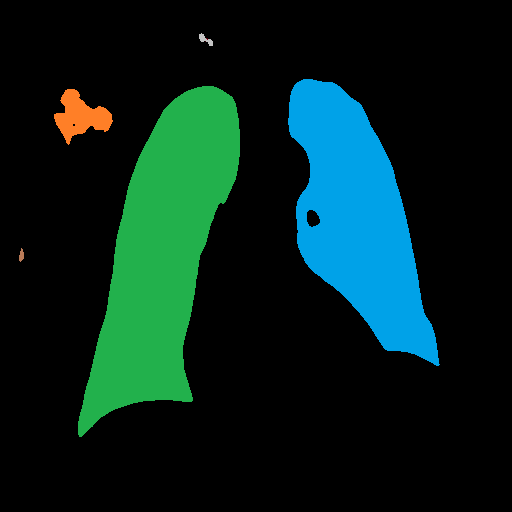

After heart and lung masks are computed, we performed dilation followed by erosion to fill holes in output mask [18], then we find the connected components of prediction masks (Figure 3).

From the lung mask, we chose the two largest connected components and disregarded others as noise. The connected component with a lower x-axis coordinate is designated as the left lung mask and the other as the right lung mask. From the heart mask, we chose the connected component larger than a given threshold and closest to the center and designate it as the heart mask.